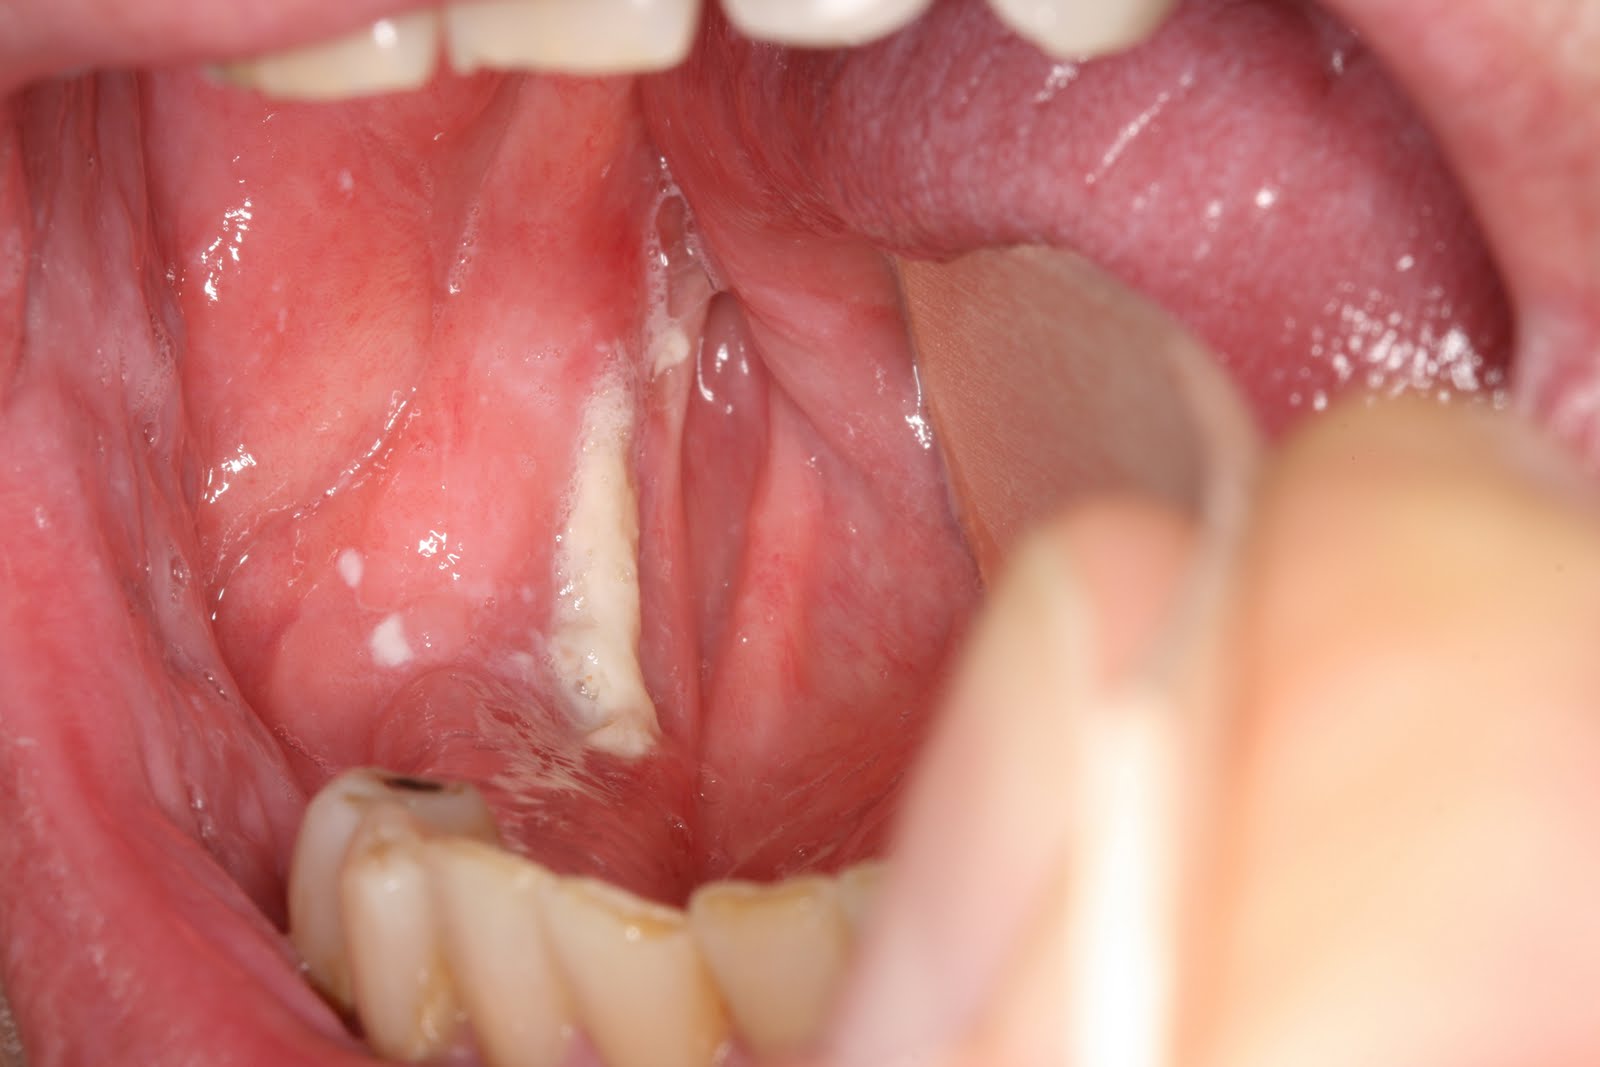

Οστεονέκρωση στην περιοχή της δεξιάς έσω λοξής γραμμής(«http://emedicine.medscape.com»)

Οστεονέκρωση των γνάθων από τη λήψη διφωσφονικών αλάτων ορίζεται ως η παρουσία αποκαλυμμένου νεκρού οστού στη γναθοπροσωπική περιοχή που επιμένει για περισσότερο απο 8 εβδομάδες σε ασθενή, χωρίς ιστορικό ακτινοβολίας στην περιοχή, αλλά με προγενέστερη ή τρέχουσα θεραπεία με διφωσφονικά. Η επίπτωση της οστεονέκρωσης από λήψη διφωσφονικών σε ασθενείς με ΠΜ, καρκίνο του μαστού και καρκίνο του προστάτη αναφέρεται 3-11% και 7-21% στις αναδρομικές και τις προοπτικές μελέτες, αντίστοιχα.

Μόνο μία περίπτωση οστεονέκρωσης δεν συνδέθηκε με την παρουσία εκλυτικού παράγοντα. Στις υπόλοιπες 19/20, διαπιστώθηκε η ύπαρξη εκλυτικού παράγοντα: εξαγωγές δοντιών (14), άλλες χειρουργικές πράξεις (2), οξύαιχμη έσω λοξή γραμμή (ανατομική θέση καλυπτόμενη από λεπτό βλεννογόνο)(3).